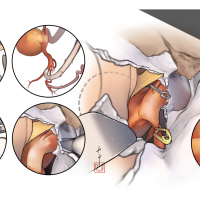

FEN2022シリーズ